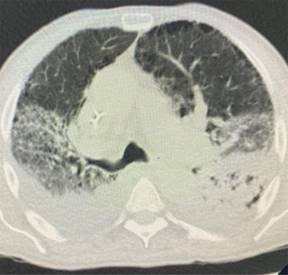

Presentamos una serie de casos de cuatro pacientes con SARS-CoV-2 con un compromiso importante de la oxigenación a pesar del uso de sistemas de alto flujo. En la Tabla 1 se describen grupos etarios, sexo, morbilidades, condiciones clínicas y escalas de severidad pronóstica de ingreso. Evolucionan tórpidamente frente al uso de cánula de alto flujo con índices de Rox por debajo de dos puntos en las primeras 12 horas.4 Se inicia ventilación mecánica no invasiva con progresión a falla respiratoria por aumento de la carga inspiratoria, por lo que requirieron protección de vía aérea. Se documenta un serio deterioro de la mecánica ventilatoria con sobredistención, aumento del trabajo respiratorio y caída de las distensibilidades; variables de monitoreo de la ventilación mecánica tomada en zona cero de flujo justo antes de cada inspiración. Adicionalmente evoluciona con importante deterioro de la ventilación minuto alveolar y de la oxigenación frente a la ventilación mecánica instaurada y a la posición prono, con poca tolerancia a la presión positiva direccionada por bucle presión volumen, meseta, fracción inspirada de oxígeno y curva presión tiempo.5-7 Con base en imágenes escanográficas que documentan infiltrados esmerilados, se describen cuatro campos pulmonares y zonas de condensación en las Figuras 1-4, además de compliance menor de 40 cm y requerimientos de PEEP entre 17 y 20 cm de agua, con el antecedente de volúmenes corregidos espiratorios durante la ventilación mecánica no invasiva entre 15 y 20 puntos se precisa SARS-CoV-2.8 Con base en la evolución descrita se decide instaurar protección pulmonar con 3 mL por kilogramo de peso más insuflación de gas traqueal con 5 L por min con el ánimo de ahorrar presión positiva de fin de espiración (PEEP por sus siglas en inglés positive end expiratory pressure), volumen tidal y velocidades de flujo. En la Tabla 2 se registra evolución gasimétrica antes y después de la estrategia. Se descartan coexistencias infecciosas de acuerdo al reporte de la microbiología. En los cuatro pacientes se documentaron defectos segmentarios de distribución vascular compatibles con enfermedad pulmonar tromboembólica. Evolucionan satisfactoriamente permitiendo desmontar estrategia de rescate con base en mecánica ventilatoria e índice de oxigenación,9 pudiendo implementar asa cerrada en asistencia proporcional con 40% de asistencia por flujo y volumen, PEEP de 10 cm y fracción inspirada de oxígeno de 50%. Se realizan monitoreos en asa cerrada que se muestran en la Tabla 3, documentándose trabajo respiratorio limítrofe, serio deterioro de las propiedades pulmonares mecánicas dinámicas y estáticas sin poder liberar de manera convencional, por lo que se programa para traqueostomía y traslado a cuidado crónico.

Figura 2: Enfermedad pulmonar intersticial esmerilada cuatro campos pulmonares. Broncograma en la língula. Colección derecha. Pequeñas bullas subpleurales.